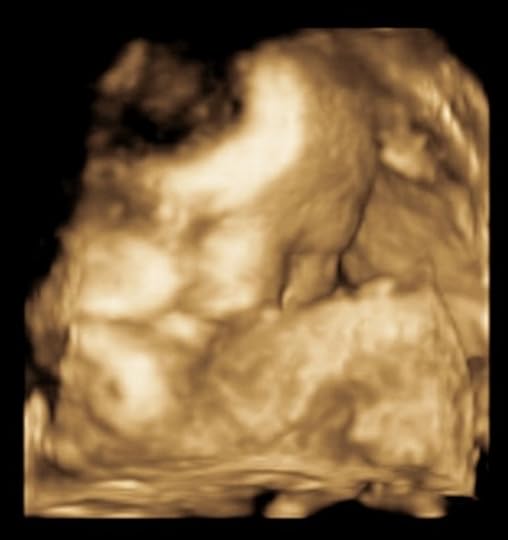

A small glimpse of Stafford's face at his 33 week ultrasound.